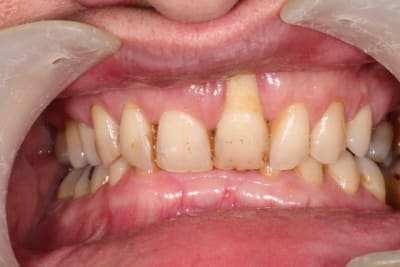

Patient adressé par une consœur pour sa 21. Fume un paquet.

Pas vraiment de pb paro, à part un bourrage entre 26 et 27 ayant entrainé une perte osseuse conséquente.

Grosse supra.

plusieurs questions :

1 : Pensez vous que la cause de la lésion soit occlusale, justement ( cela aurait pu débuter comme sur la 11, flèche rouge ) ?

2 : quid de la jonction avec le canal nasopalatin ( flèche verte ) ?

3 : après extraction, grosse perte tissulaire a prévoir. si reconstruction osseuse, il n'y aura pas un problème de tissus mou ? , faut il épaissir et faire une greffe de conjonctif avant greffe osseuse ?